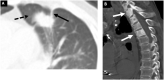

The role of imaging in cancer diagnosis and treatment has evolved at the same rapid pace as cancer management. Over the last twenty years, with the advancement of technology, oncology has become a multidisciplinary field that allows for researchers and clinicians not only to create individualized treatment options for cancer patients, but also to evaluate patients' response to therapy with increasing precision. Familiarity with these concepts is a requisite for current and future radiologists, as cancer imaging studies represent a significant and growing component of any radiology practice, from tertiary cancer centers to community hospitals. In this review we provide the framework to teach cancer imaging in the era of genomic oncology. After reading this article, readers should be able to illustrate the basics cancer genomics, modern cancer genomics, to summarize the types of systemic oncologic therapies available, their patterns of response and their adverse events, to discuss the role of imaging in oncologic clinical trials and the role of tumor response criteria and to display the future directions of oncologic imaging.